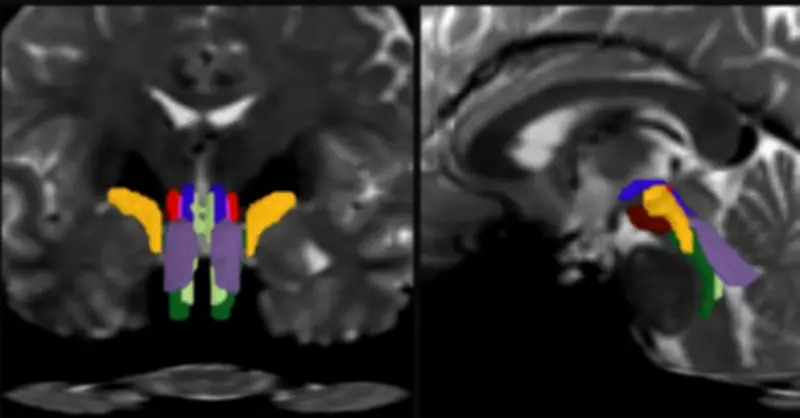

Cộng hưởng từ khuếch tán là kỹ thuật cho phép theo dõi sự khuếch tán của nước dọc theo các sợi trục thần kinh, vốn được bao bọc bởi lớp myelin giàu chất béo tạo nên “chất trắng” của não. Tuy nhiên, việc tách riêng từng bó sợi trong thân não vẫn là thách thức lớn. BSBT được thiết kế để vượt qua rào cản này với quy trình hai bước:

- Thuật toán trước tiên dựng bản đồ xác suất các bó sợi đi từ những vùng não lân cận như đồi thị và tiểu não xuống thân não.

- Sau đó, một mạng nơ-ron tích chập tích hợp bản đồ này với nhiều lớp dữ liệu hình ảnh khác để phân biệt tám bó sợi riêng biệt.

Để huấn luyện mô hình, nhóm nghiên cứu sử dụng 30 bộ dữ liệu diffusion MRI từ Dự án Human Connectome, được chú thích thủ công nhằm “dạy” AI nhận diện chính xác các bó sợi. Kết quả được kiểm chứng bằng cách so sánh với các mẫu giải phẫu não người sau tử vong, vốn được phân định rõ dưới kính hiển vi hoặc qua hình ảnh siêu phân giải.

Sau giai đoạn huấn luyện, BSBT có thể tự động xác định tám bó sợi trong các bộ dữ liệu mới. Khi thử nghiệm trên 40 tình nguyện viên được chụp hai lần cách nhau hai tháng, công cụ này liên tục xác định chính xác cùng một hệ bó sợi ở mỗi cá nhân. Nhóm nghiên cứu cũng kiểm tra chéo trên nhiều bộ dữ liệu độc lập và đánh giá riêng từng thành phần của mạng nơ-ron để bảo đảm độ tin cậy.